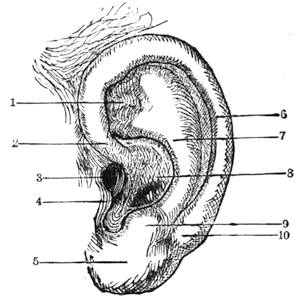

| CHAPTER XV.—ACOUSTICS. | |

| The Ear and Hearing—Physiology of Hearing and Sound—Sound as Compared with Light—What is Sound?—Velocity of Sound—Conductibility—The Harmonograph | 166 |